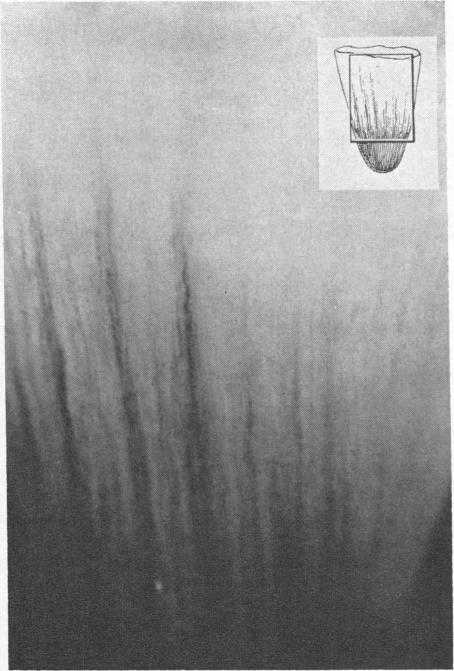

AN IN VITRO DEMONSTRATION IN INCREASED COLLECTING TUBULAR PERMEABILITY TO UREA IN THE PRESENCE OF VASOPRESSIN.

J Clin Invest. 1964 Oct;43(10):1968-75. doi: 10.1172/JCI105070.